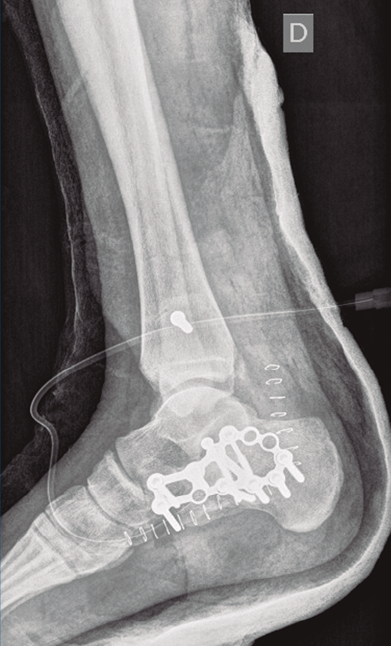

Se dio de alta el día siguiente a la cirugía con un buen control analgésico. En la radiografía de control postoperatoria presentó una correcta reducción tanto de la fractura de calcáneo como de la articulación tibioperoneo astragalina (Figuras 9 y 10). Se citó en consultas externas 2 semanas después para la retirada de la sutura, presentado un buen aspecto las heridas quirúrgicas (Figura 11), y para la colocación de un botín de yeso. Dicho botín fue retirado al mes y medio de la cirugía, colocándose una ortesis estabilizadora de tipo Walker y autorizándose la carga parcial y progresiva, comenzando la rehabilitación.

A los 9 meses únicamente presentó dolor ocasional al nivel de la articulación subastragalina y molestias en la planta del pie al deambular descalzo, por lo que se pauta plantilla amortiguadora, con la que mejora notablemente la sintomatología. Presentó una puntuación de 83 sobre 100 en la escala de la American Orthopaedic Foot and Ankle Society (AOFAS), ligeramente superior a la media descrita en estudios previos(2,3). Radiográficamente se evidenció una anatomía restablecida del calcáneo y de la sindesmosis, así como una altura adecuada de ambos tobillos (Figuras 12 y 13). Dada la buena evolución, se decidió continuar con el seguimiento anual del paciente sin realizar la extracción del material de osteosíntesis, para valorar la necesidad de una futura artrodesis sub­astragalina.

Figura 13. Radiografía anteroposterior de ambos tobillos a los 9 meses de la cirugía.